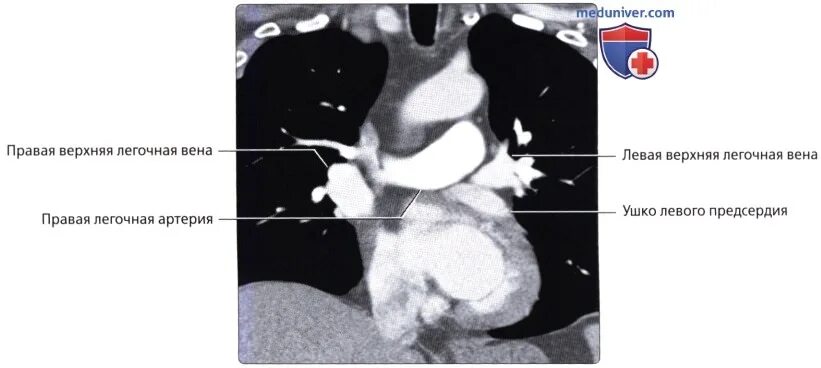

Легочный ствол легкого